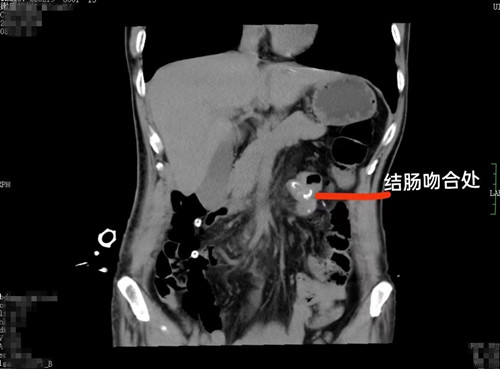

68岁的李爷爷平素身体硬朗,前些日子感觉小腹隐痛,到医院检查患上了泌尿系结石,遂准备在湖南省人民医院泌尿外科进行手术碎石。没想到术前详细检查时,发现横结肠肿瘤性病变,最终确诊结肠癌,接受了手术治疗。

在泌尿四病区和普外三病区的联手下,李爷爷先接受了钬激光碎石手术,又接受了腹腔镜下右半结肠癌根治术。看到术后病理结果,李爷爷终于相信自己是患了结肠癌,心理防线彻底被击垮,开始抗拒治疗,闹着要拔管出院。